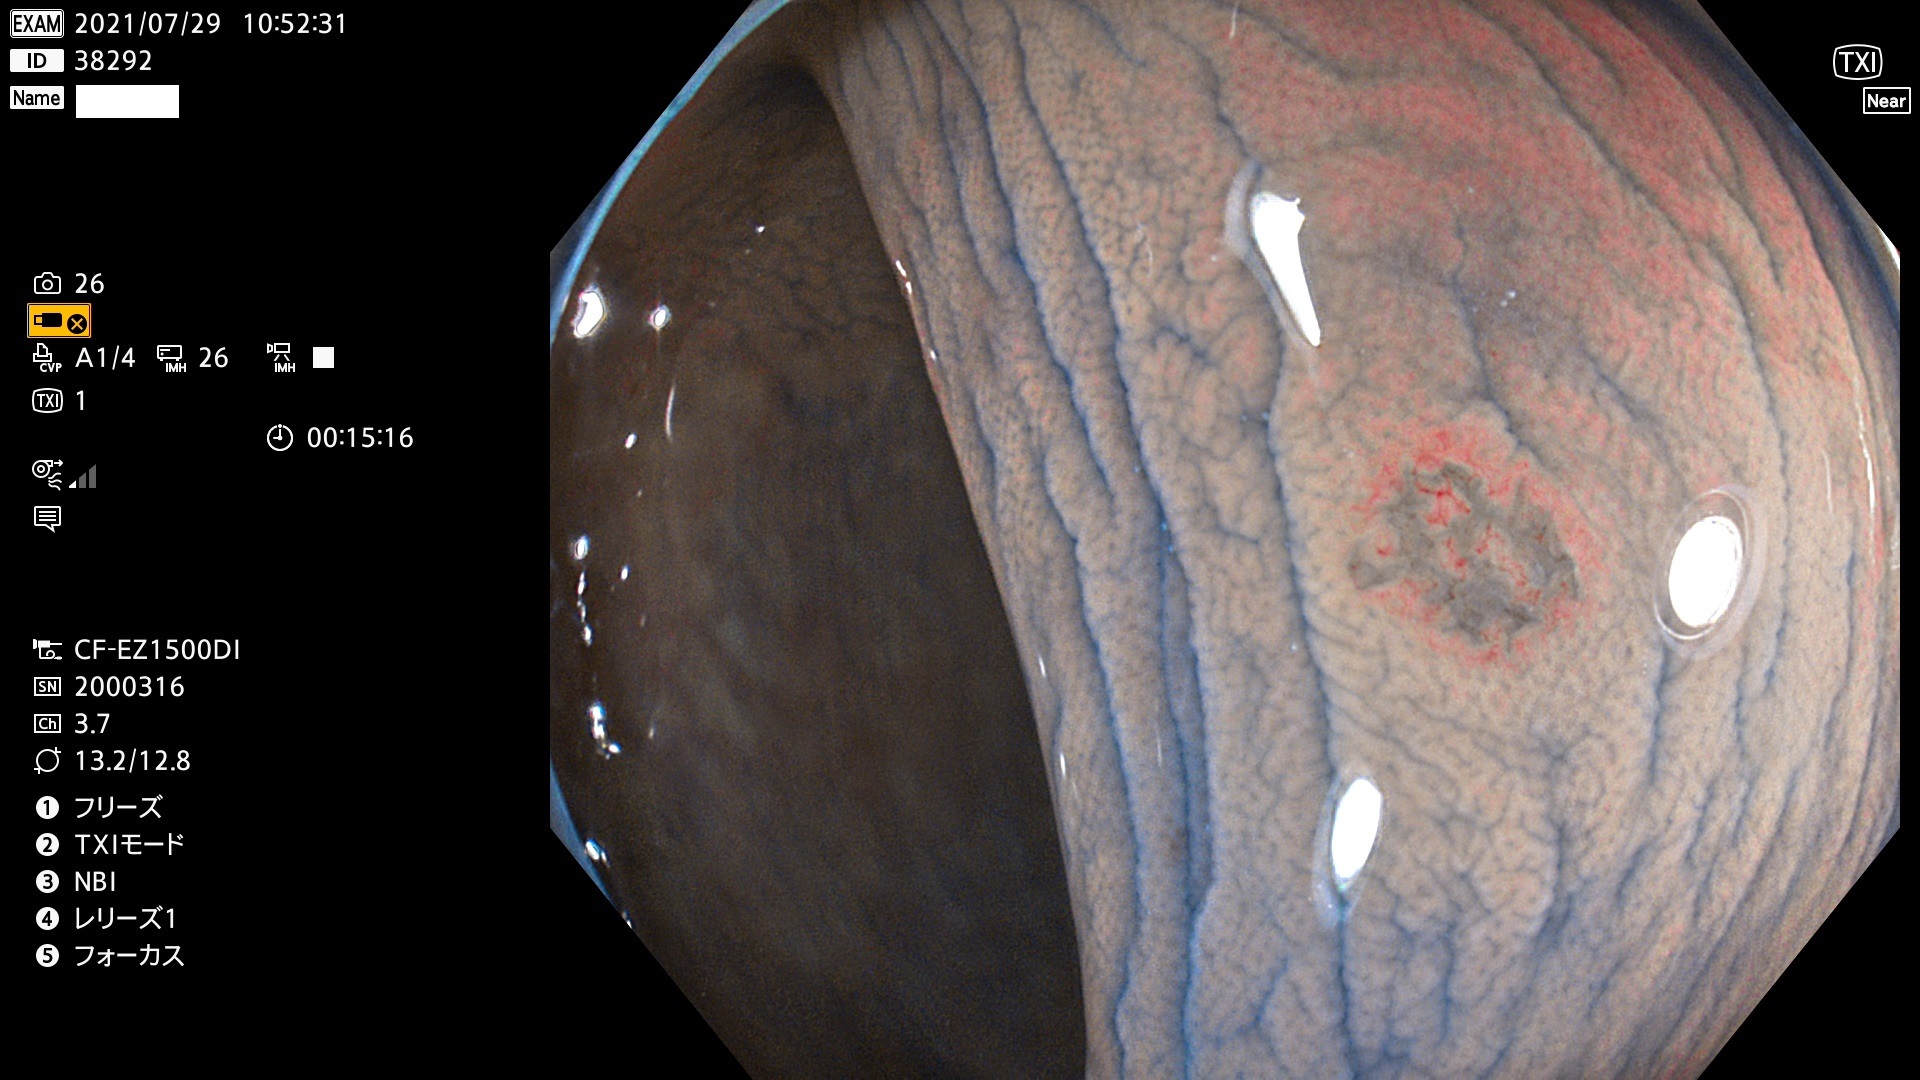

発見困難で危険性の高い平坦型病変(上記100名より抽出)